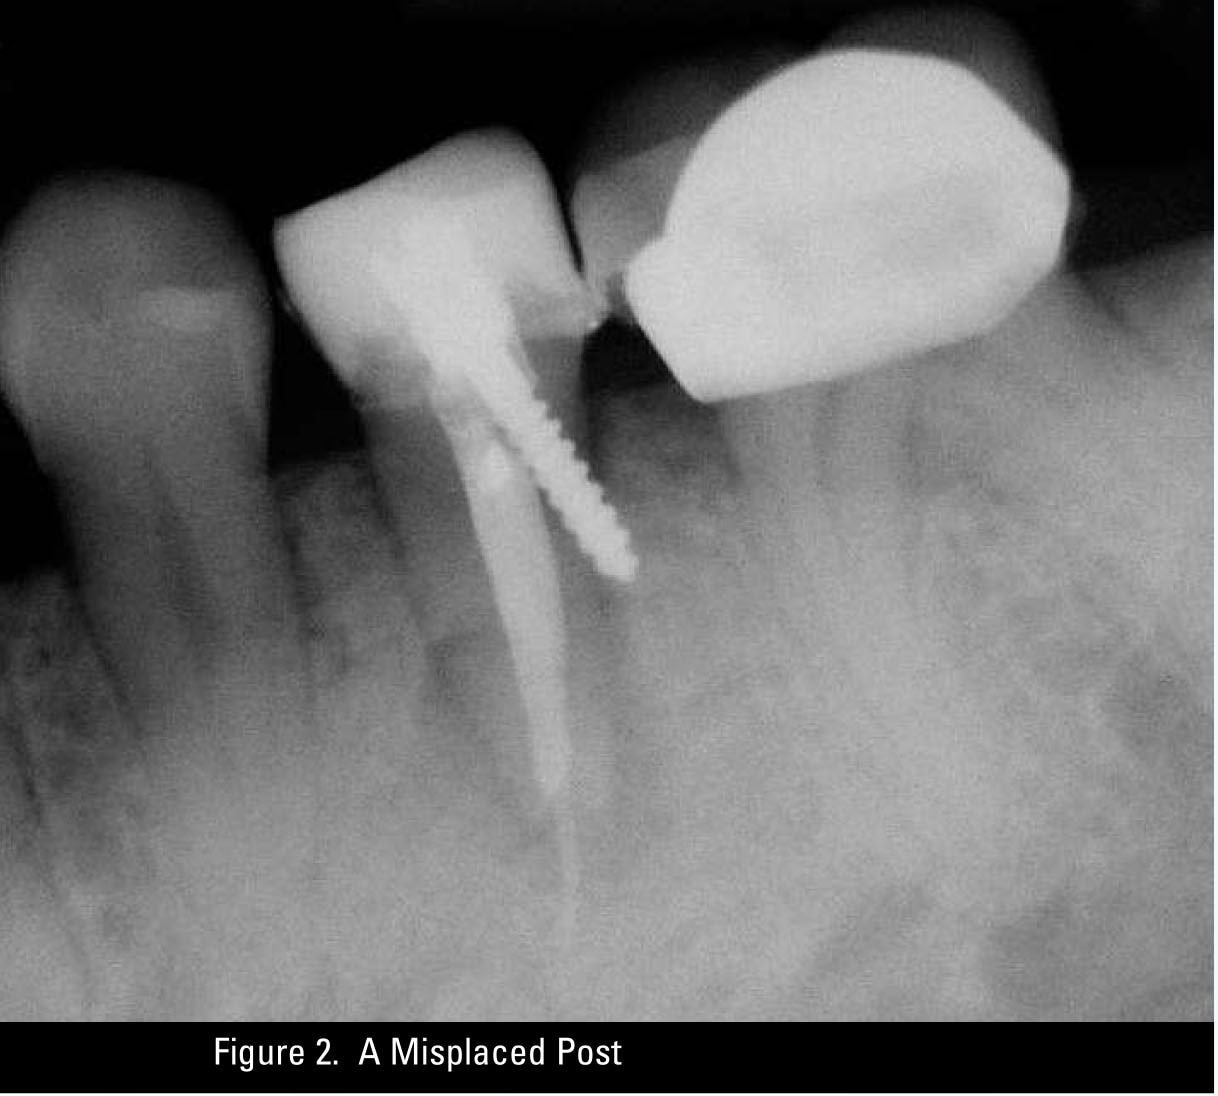

A Misplaced Post

A final observation is that the old adage that a picture is worth a thousand words is certainly true in dental radiology. A single radiograph may end up being the piece of information that actually helps plaintiff’s counsel to establish that there was indeed a deviation from the standard of care in treatment provided. By way of example, see Figure 2, a misplaced post, and Figure 3, over-exuberance in the use of sealant in endodontic therapy.